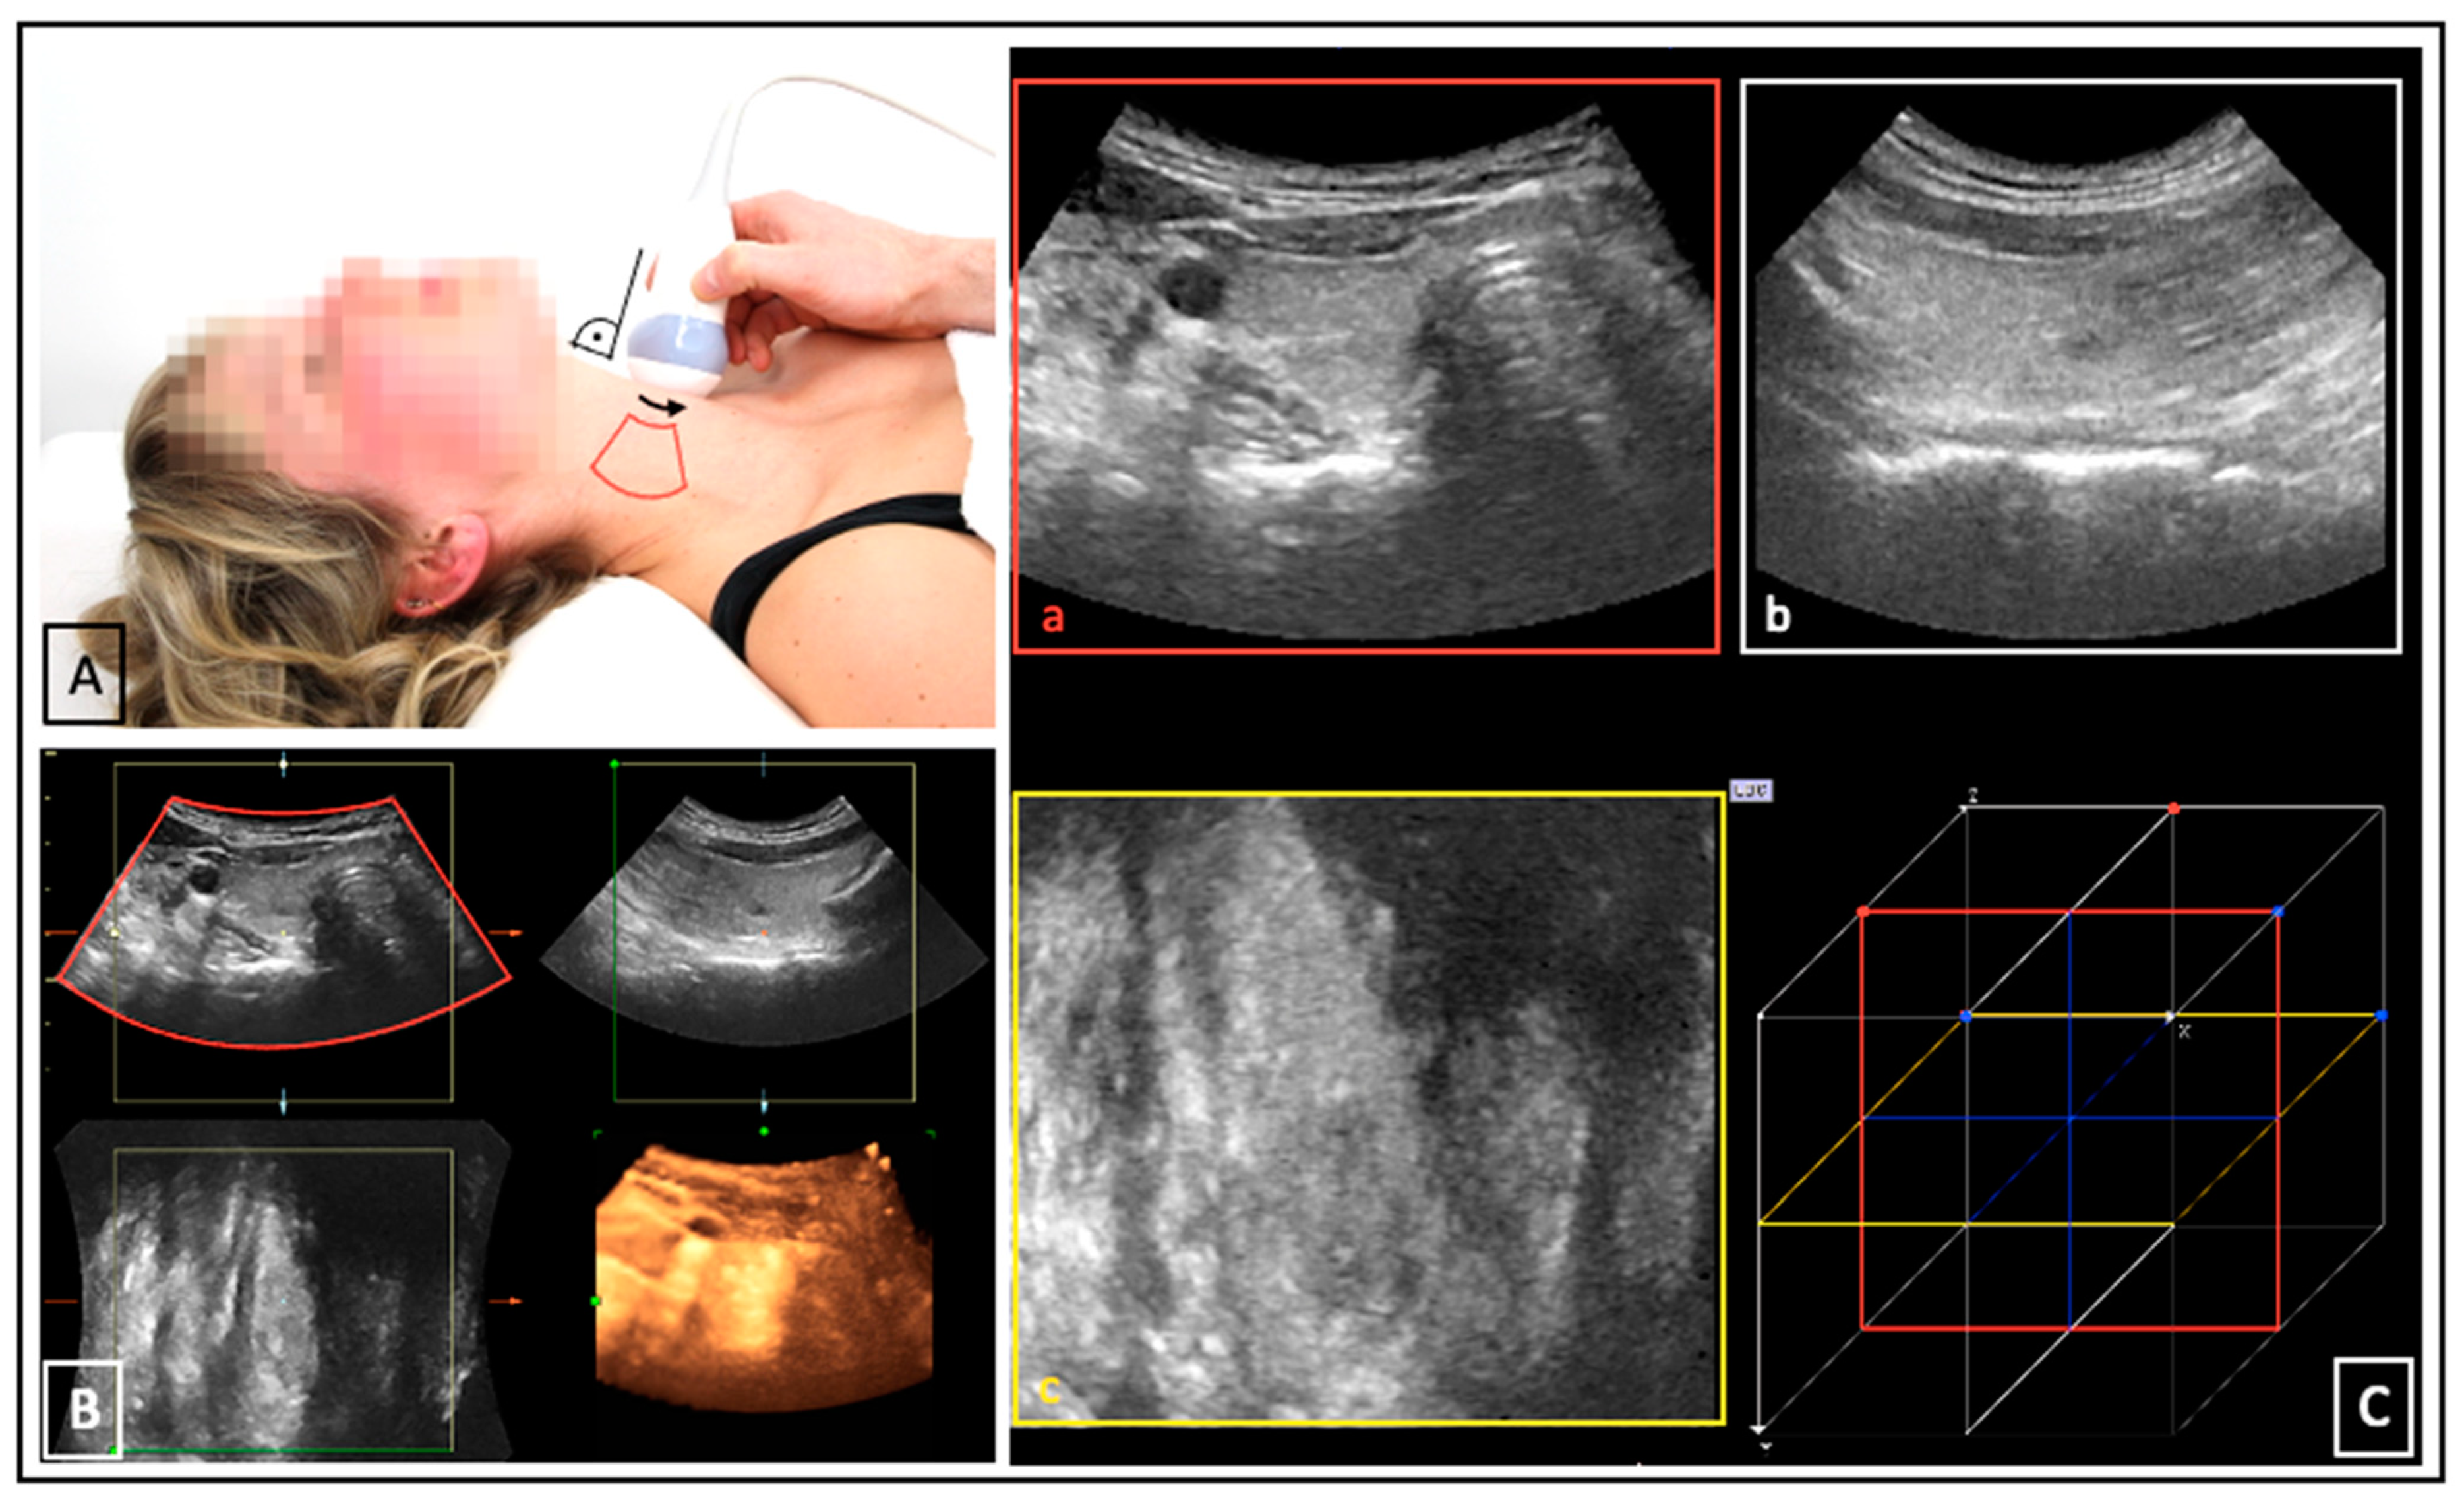

US was performed on the LOGIQ E9 device (GE Medical Systems, Milwaukee, WI, USA). Separate scans of each thyroid lobe (left and right) were acquired. ConUS was conducted with the linear matrix array ML6-15 according to a local standard operating procedure [7]. For 3DsnUS, a magnetic field and specific position sensors equipped to the ML6-15 probe were necessary. For 3DmsUS an automated mechanically swept 3D convex probe (RAB4-8) was used. The methodology of these 3D-US applications has been described in several previous publications [14,19,20]. All 3D-US data sets were transferred to the research software PMOD (Version 4.1, PMOD Technologies Ltd., Zürich, Switzerland). Examination settings and acquired data sets are depictured in Figure 1 and Figure 2.

Figure 1.

3DsnUS: probe movement ((A), black arrow) within the magnetic field generated by a transmitter ((A), red arrow); position sensors ((A), blue arrows) enable reconstruction of 3DsnUS images based on the probe movement and according to the position of the associated 2D frames ((A,B), black, blue, and red boxes). (C) shows a 3DsnUS data set of a right thyroid lobe displayed in the PMOD software in three dimensions: transverse ((C), a, red box), sagittal ((C), b, white box), coronal ((C), c yellow box).